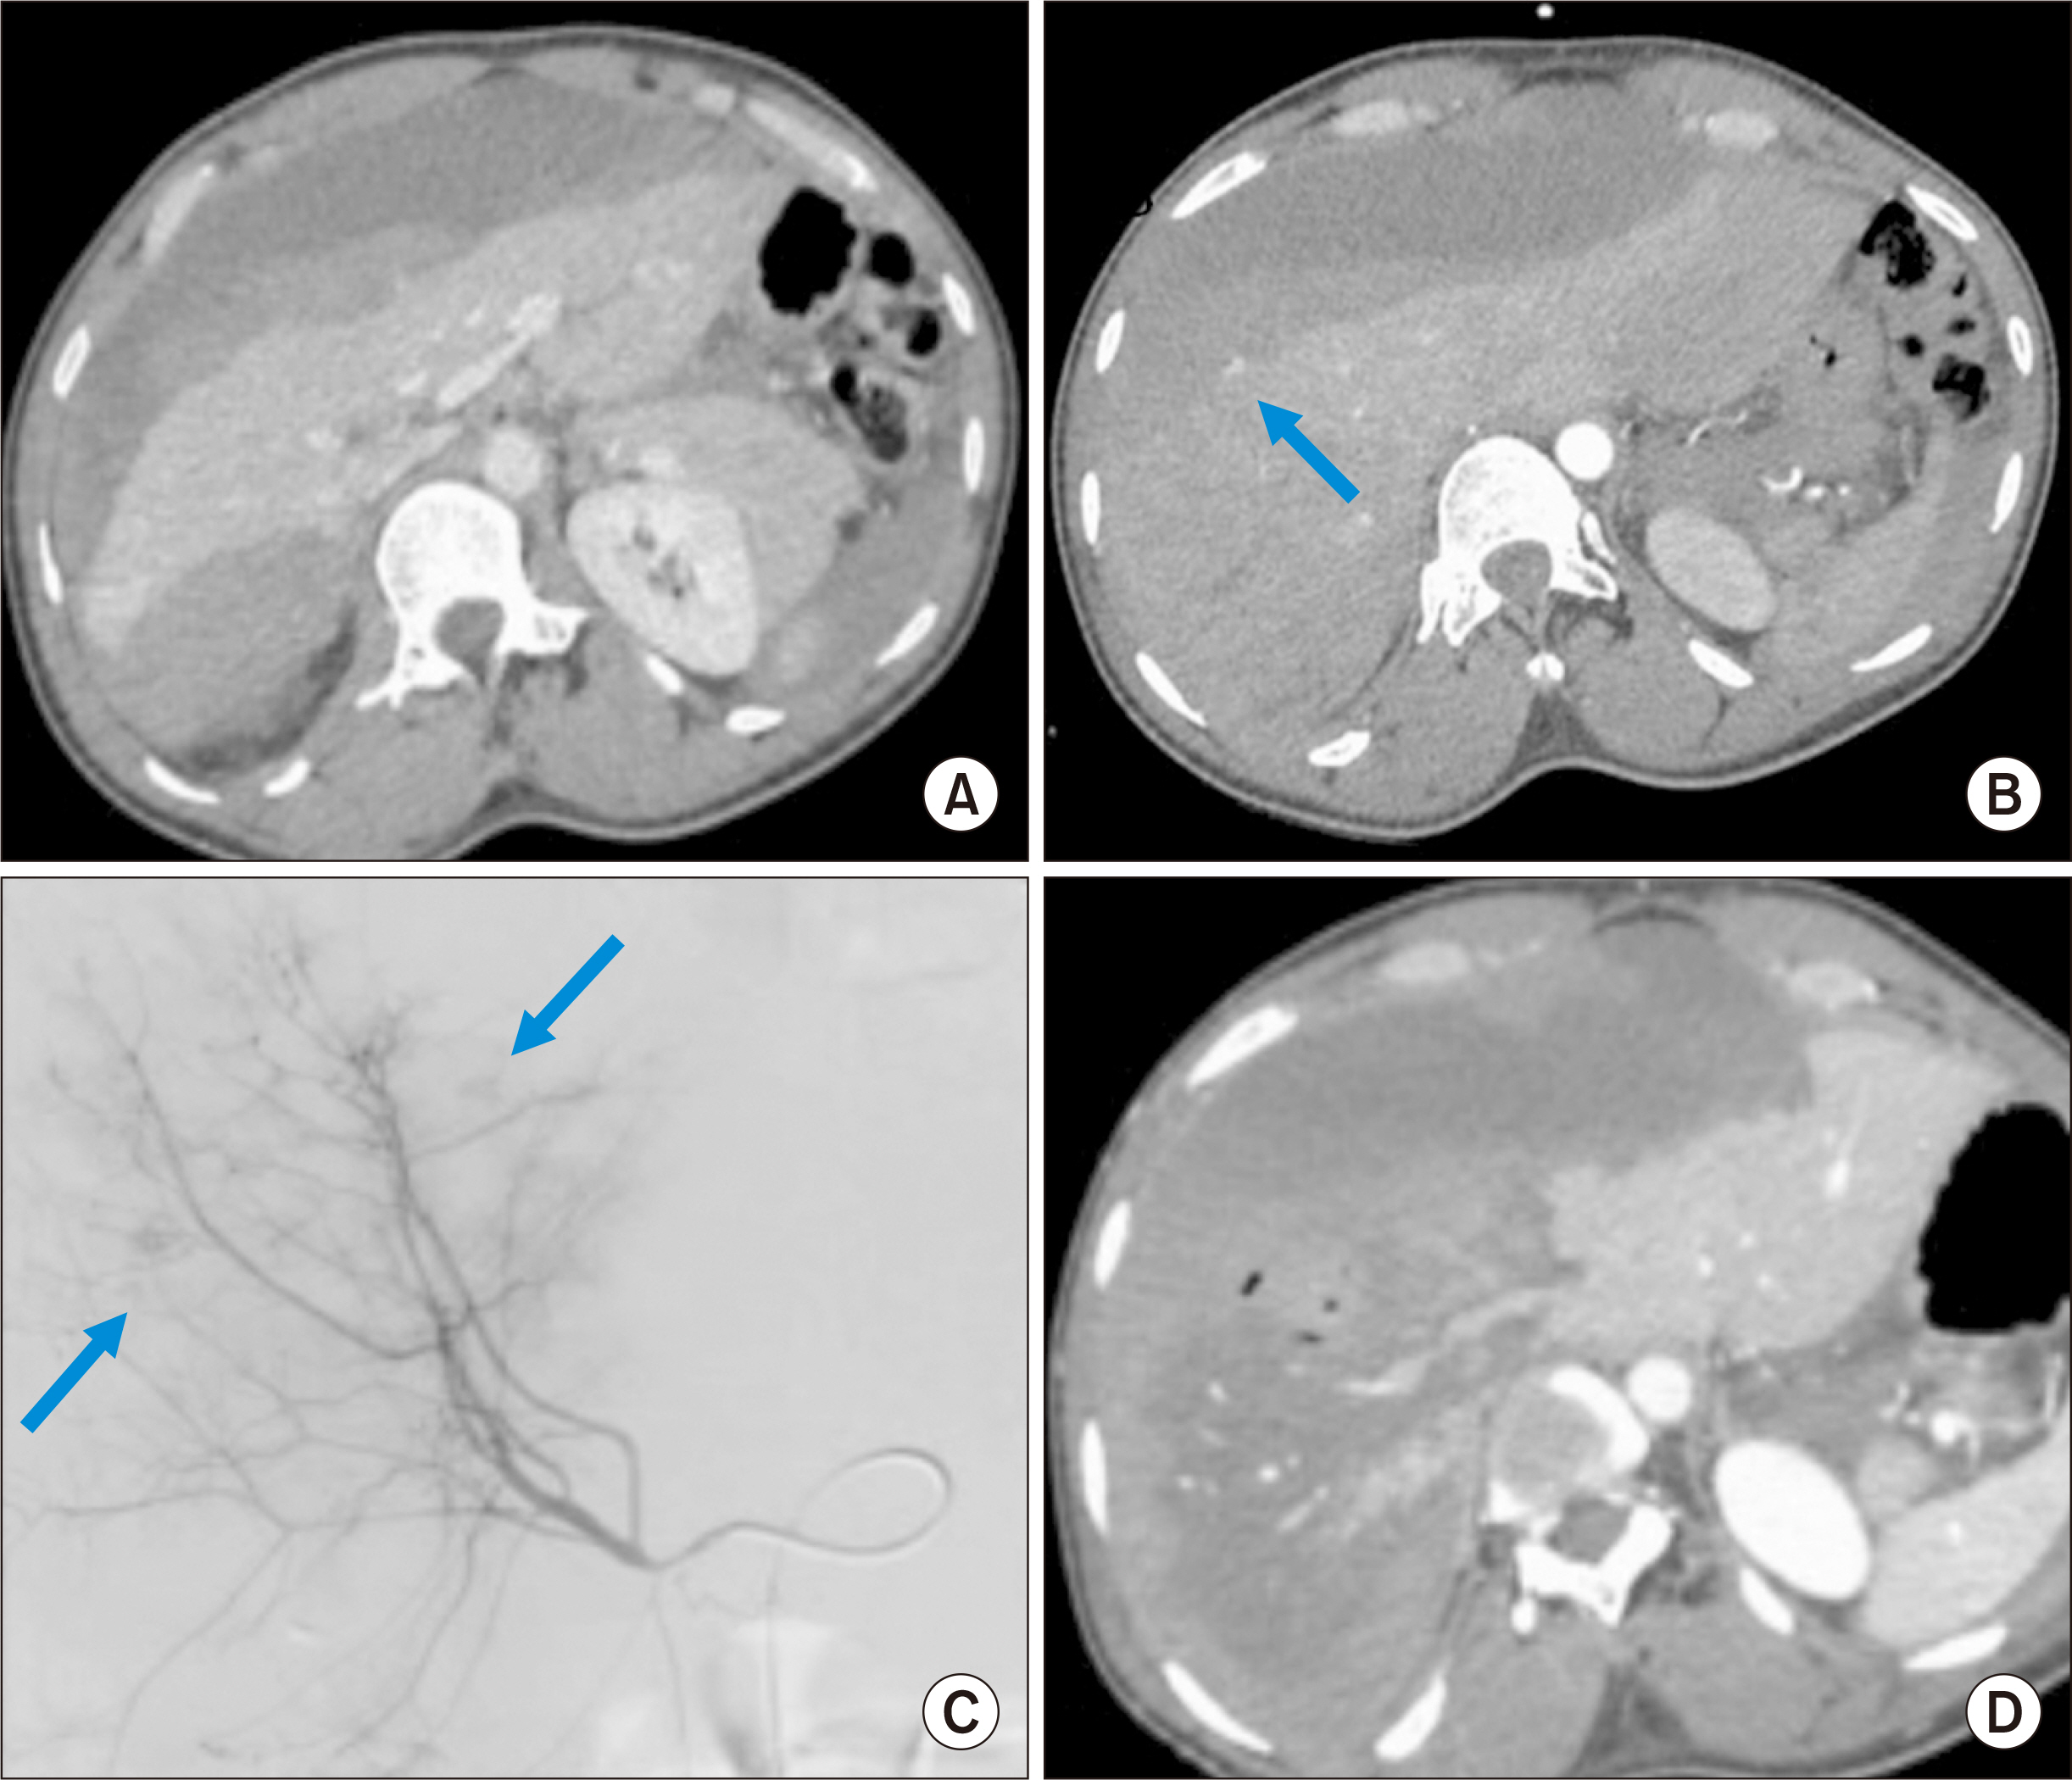

- Hepatic compartment syndrome (HCS) is a rare but life-threatening entity that consists of a decreased portal flow due to intraparenchymal hypertension secondary to subcapsular liver hematoma. Lethal liver failure can be observed. We report three cases, and review the literature. A 54-year-old male was admitted for extensive hepatic subcapsular hematoma after blunt abdominal trauma. Initially, he underwent embolization of the hepatic artery’s right branch, after which he presented clinical deterioration, major cytolysis (310 times the upper limit of normal [ULN]), and liver failure with a prothrombin time (PT) at 31.0%. A 56-year-old male underwent liver transplantation for acute alcoholic hepatitis. On postoperative day 2, he presented a hemorrhagic shock associated with deterioration of liver function (cytolysis 21 ULN, PT 39.0%) due to extensive hepatic subcapsular hematoma. A 59-year-old male presented a hepatic subcapsular hematoma five days after a cholecystectomy, revealed by abdominal pain with liver dysfunction (cytolysis 10 ULN, PT 63.0%). All patients ultimately underwent urgent surgery for liver capsule excision, hematoma evacuation, and liver packing, if needed. The international literature was screened for this entity. These three patients’ outcomes were favorable, and all were alive at postoperative day 90. The literature review found 15 reported cases. HCS can occur after any direct or indirect liver trauma. Surgical decompression is the main treatment, and there is probably no place for arterial embolization, which may increase the risk of liver necrosis. A 13.3% mortality rate is reported. HCS is a rare complication of subcapsular liver hematoma that compresses the liver parenchyma, and leads to liver failure. Urgent surgical decompression is needed.